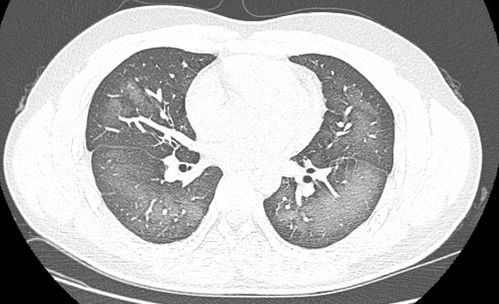

肺部变白并不是一种具体的疾病,而是一种影像学表现,在X光、CT等检查中,肺部变白可能由以下原因引起:

肺炎:肺炎是肺部感染的一种常见疾病,炎症会导致肺部组织密度增加,在X光片上呈现为白色阴影,肺炎通常可以通过抗生素治疗,预后良好。

肺气肿:这是一种慢性肺部疾病,肺部气体交换功能下降,可能导致肺部透亮度增加,看起来“变白”,肺气肿通常与吸烟有关,虽然无法根治,但通过治疗可以控制症状。

肺纤维化:这是一种肺部组织瘢痕化的疾病,会导致肺部变硬、变厚,在影像上可能呈现白色,肺纤维化目前尚无特效治疗方法,但早期干预可以延缓病情进展。

肺结核:结核病是一种由结核分枝杆菌引起的感染,可能在肺部形成白色病灶,通过规范的抗结核治疗,大多数患者可以康复。

肺癌:虽然肺癌在影像上可能表现为白色阴影,但并非所有肺部变白都是肺癌,肺癌的诊断需要结合其他检查,如活检等。